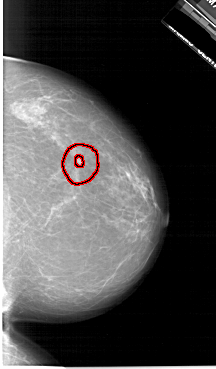

A_1620_1.LEFT_MLO

LEFT_MLO LINES 6586 PIXELS_PER_LINE 3316 BITS_PER_PIXEL 12 RESOLUTION 43.5 NON_OVERLAY

FILE: A_1620_1.RIGHT_MLO.OVERLAY

TOTAL_ABNORMALITIES 1

ABNORMALITY 1

LESION_TYPE MASS SHAPE IRREGULAR MARGINS SPICULATED

ASSESSMENT 5

SUBTLETY 3

PATHOLOGY MALIGNANT

TOTAL_OUTLINES 2

BOUNDARY

CORE